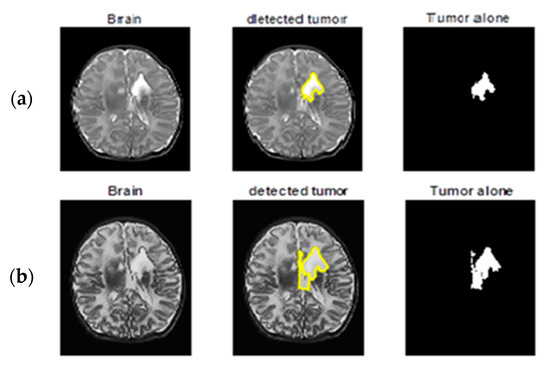

Segmentation results of the proposed method are shown in Figure 11 and Figure 12. The obtained numerical values are tabulated in Table 5 and Table 6 respectively, including the performance measures of dice similarity and Jaccard index. The proposed method provides efficient and robust results when compared to the FCM technique by a mean of a 98.86% dice index and 96.9% Jaccard index. This helps the physician to check whether the presence of any abnormalities is available in the MRIs corresponding to different parts of the brain. We conclude that the proposed remodified FCM technique ARKFCM method is more robust to noise and shading effects; the major advantage of using this technique is locating the tumor and affected regions.

Figure 11.

Tumor detection from original MRI brain images. (a) the first image in the is the original image, the second image is the segmentation image of the first image after preprocessing, and the third image represents detection of tumor alone. (b–d) rows consists of original brain images, segmented image with detected tumor, segmented tumor alone with proposed method respectively.

Figure 12.

In the figures, the first image in the is the original image, the second image is the segmentation result of the first one, and the third image represents the extraction of the tumor succeeding segmentation. Similarly, in Figure 12, row 2 (b), the first figure is the preprocessed result of the original image, and the second and third images are same as above. From the third part, it is visualized with ease that the result of the tumor extraction does have more precision in the case of part ‘(b)’ compared to part ‘(a)’.